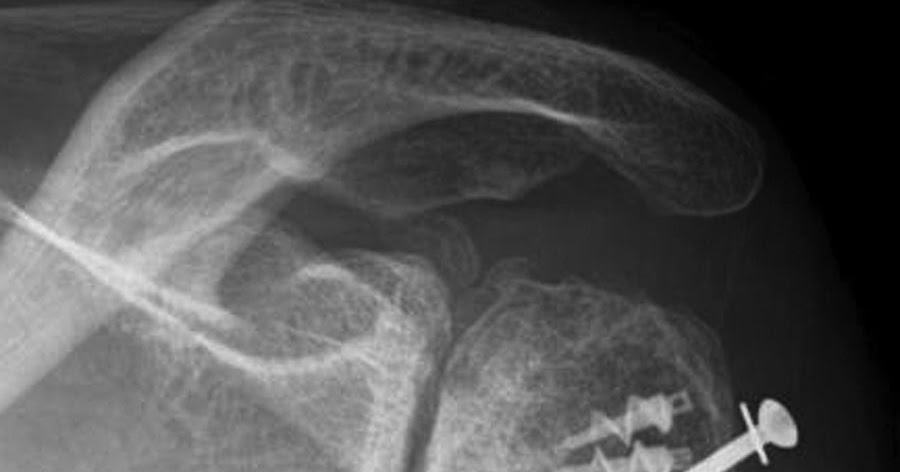

The basic principles of shoulder arthroplasty in post traumatic arthritis are similar to those in degenerative arthritis but some important differences exist because of scarring and deformity. It’s usually a temporary issue, and many people recover in a few months. Swelling and pain can occur due to fluid building up in the joint.

This event can be a traumatic shoulder dislocation, a severe fall onto the shoulder, or a fracture. To suppress the natural tendency of most patients to immobilize the painful joint until comfort returns. Although this type of arthritis is triggered by physical trauma that damages a joints cartilage or bone, the condition itself is actually a form of osteoarthritis.

What kinds of arthritis affect the shoulder? M19.11 should not be used for reimbursement purposes as there are multiple codes below it that contain a greater level of detail. Therefore, a patient older than 40, seen shortly after a shoulder injury, should be encouraged to use the arm as normally as possible with movement to full range at least twice daily.

I had to have total shoulder replacement surgery last week. That injury can be in the hands or feet, shoulders or knee. After conservative treatments failed to relieve her symptoms, the patient underwent stemless total shoulder arthroplasty (tsa) because of.